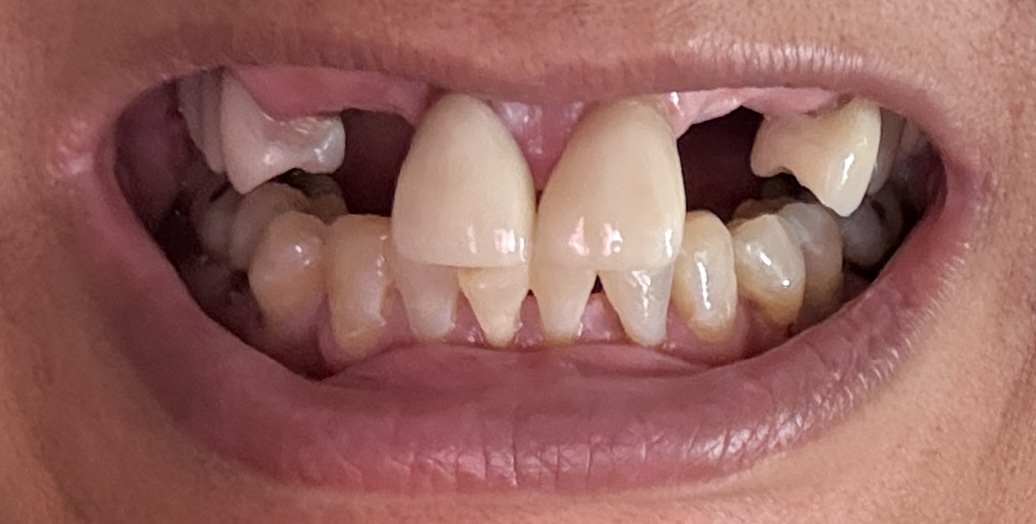

Overall information (upper arch)

12,13,14 have had root canals in past and now have quite a bit movement. 2-5 have all had root canals in past and now the crowns are breaking down.

Overall information (lower arch)

Overall, all of my gums have receded and most of the bottom teeth are exposed w/ some roots and there are many cavities.